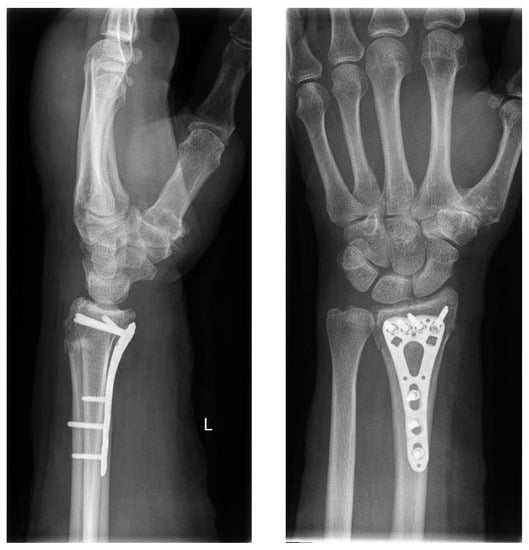

In accordance with the hospital’s standard procedure, first, the fractured forearm was lifted by finger-trap traction and was then reduced. The reduced fracture was then splinted with a circular cast or an orthosis (OPTIVOhand, OPED GmbH, Valley, Germany). After the traction was lifted, another radiograph was obtained. If an intra-articular fracture was suspected, a computed tomography (CT) scan was performed. Palmar plate osteosynthesis was performed in all patients after the swelling had subsided (VA-LCP, Synthes GmbH, Oberdorf, Switzerland; or Aptus, Medartis AG, Basel, Switzerland, Figure 2).

Figure 2.

Standard operative treatment with palmar plate.